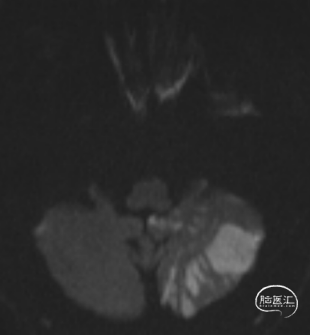

术后头晕呕吐,当日DWI:左侧小脑梗死,MRA未见明显大血管栓塞。

术中即刻发现出现栓子脱落左椎动脉闭塞,立即予替罗非班负荷量并置入支架。后续复查左侧小脑虽有梗死病灶,但患者神经功能无缺损,头晕症状完全消失,下肢拖曳也完全消失,生活完全恢复至正常。